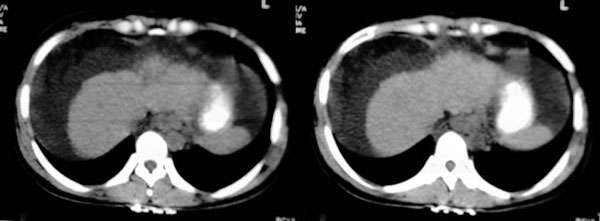

大家好,还有就是她的胆囊在哪?那肝右前间隙液体内环状稍高密度是什么,又为什么壁欠光滑.请大家再帮忙看看.

肝右前间隙液体内环状稍高密度,请查附件看有没有肿瘤。

肝右前间隙液体内环状稍高密度,不会就是胆囊吧?

支持肝硬化、腹水、脾稍大。肝脏与前腹壁的环状影考虑是胆囊及胆囊结石。

支持肝硬化、腹水、脾大。,另腹水内漂浮的圆形阴影考虑:1 胆囊 2 大量腹水后继发感染形成脓肿。